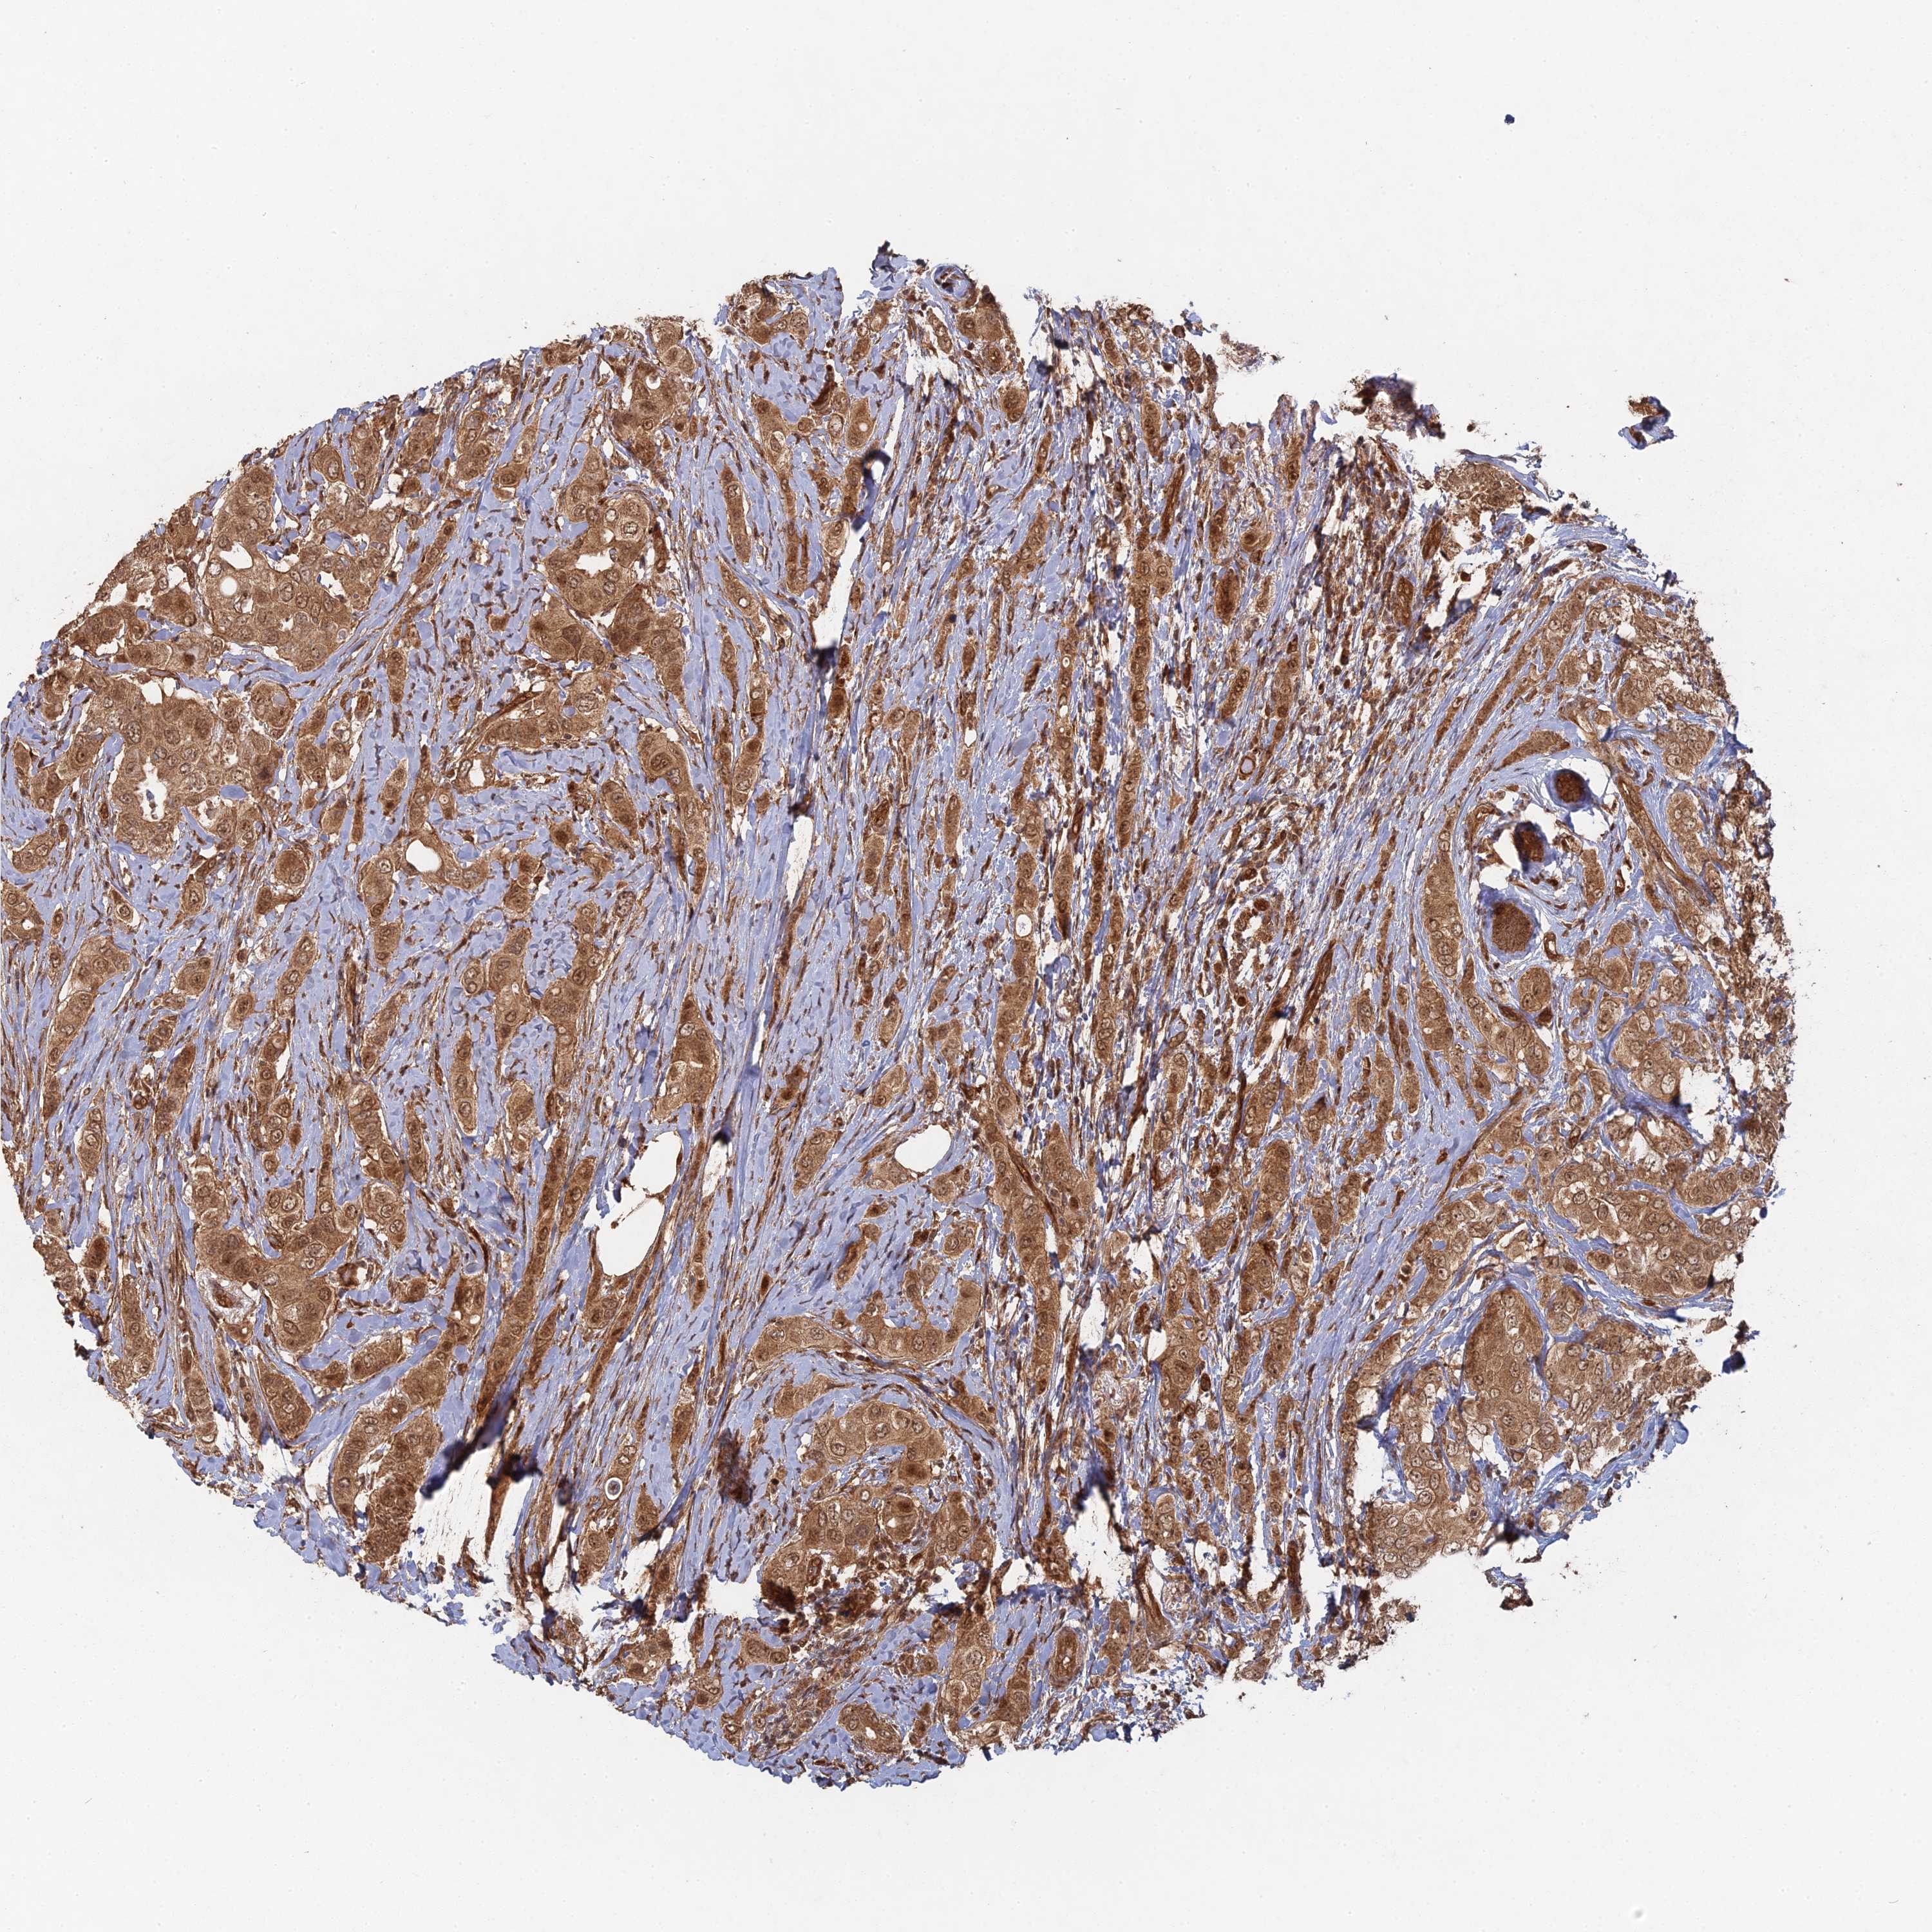

BRCA TCGA BRCA VALIDATION PROTEIN EXPRESSION